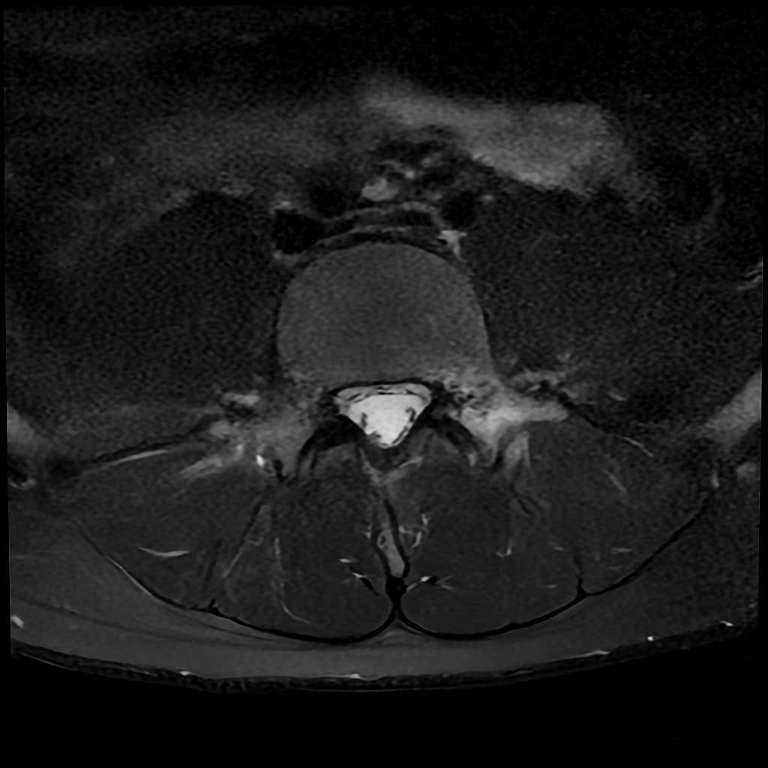

整形外科領域

脊椎

分離症